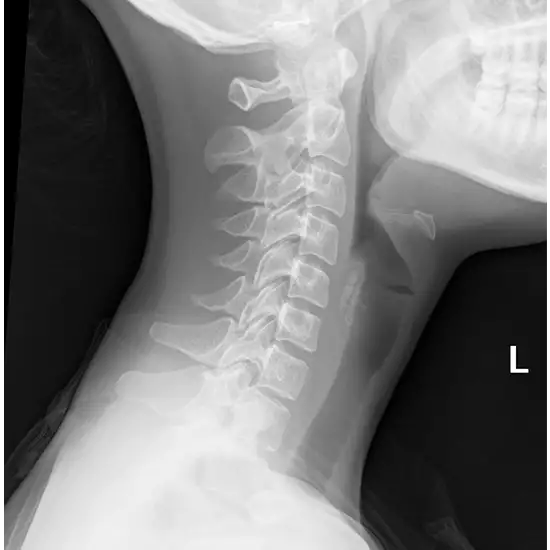

X-ray Neck AP LAT View Test is used to determine the existence of a cervical fracture after head and neck trauma. It is used to determine the source of back or neck discomfort. In an Anterior-Posterior (AP) projection, X-rays flow from the patient's front to their back. The lateral view is obtained from the patient's side.

• To diagnose neck injuries, numbness, discomfort, and arm weakness.

• To identify fractures, dislocations, and windpipe swelling.

• For diagnosis of (bone thinning) osteoporosis, neck bone tumor/cyst, neck disc and joint damage (cervical spondylosis)

• To determine spinal abnormalities, vocal cord enlargement (croup), epiglottitis, tonsillitis, adenoids, and foreign object obstruction in the throat.